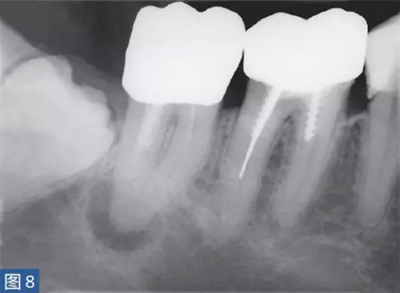

急性根尖周膿腫(AAA acute apical abscess)

急性根尖膿腫(圖8 和9)是一種局部的或者彌漫性的液性病變。由壞死牙髓產(chǎn)生的微生物和非微生物刺激所引起的嚴(yán)重炎癥反應(yīng)造成了根尖周組織的破壞。患者通常表現(xiàn)出中度至重度疼痛,根據(jù)嚴(yán)重程度還可能出現(xiàn)發(fā)熱和白細(xì)胞增多的全身癥狀。

臨床診斷顯示牙髓電活力測(cè)試結(jié)果陰性。叩診和觸診通常會(huì)引起疼痛。如果膿腫僅限于骨內(nèi),則不出現(xiàn)腫脹癥狀。放射學(xué)檢查,根尖周組織表現(xiàn)從無(wú)變化到發(fā)生明顯變化。

圖8:47 牙齒AAA。術(shù)前X 線片?;颊呔驮\時(shí)有發(fā)燒癥狀,且叩診和觸診疼痛明顯。